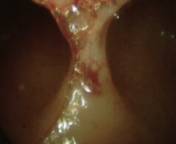

Histeroskopide rahim içi

yapışıklığın görünümü